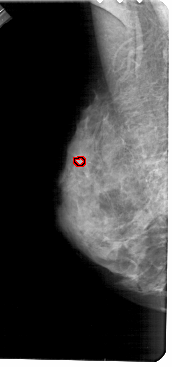

A_1684_1.LEFT_MLO

FILE: A_1684_1.LEFT_MLO.OVERLAY

TOTAL_ABNORMALITIES 1

ABNORMALITY 1

LESION_TYPE CALCIFICATION TYPE PLEOMORPHIC DISTRIBUTION CLUSTERED

ASSESSMENT 4

SUBTLETY 2

PATHOLOGY BENIGN

TOTAL_OUTLINES 1

BOUNDARY